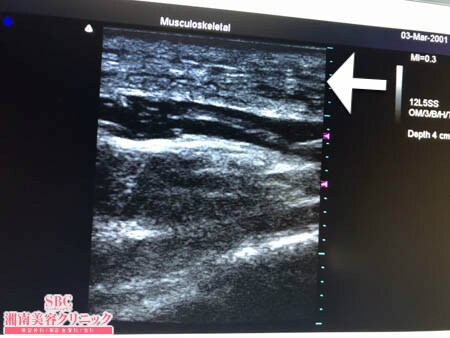

No.234335【脂肪吸引】【動画あり】湘南美容外科脂肪吸引最高責任者である竹田先生による脂肪吸引のフォトギャラリー!他院の再手術!15kgダイエットの後のリバウンドで脂肪吸引を決意!術中3Dタッチビュー・右肩甲骨横